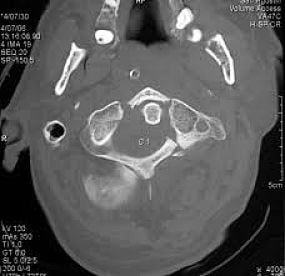

La columna cervical tienen tres características principales que las distinguen de otras vértebras:

- Agujero vertebral triangular.

- Apófisis espinosa bífida: aquí es donde el proceso espinoso se divide en dos distal (debemos recordar que proceso y apófisis tienen el mismo significado en anatomía.

- Agujeros transversal: orificios en los procesos transversales. Dan paso a la arteria vertebral, vena y nervios simpáticos.